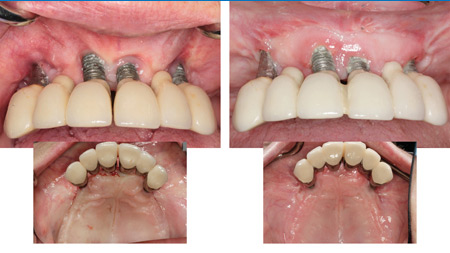

The Best of Both Worlds: A Hybrid Digital-Analog Workflow for a Maxillary Full-Arch Implant-Supported Prosthesis

Full arch implant-supported fixed protheses have become a highly desired solution for the rehabilitation of patients with terminal dentition or completely edentulous arches. New developments in digital dentistry have enabled practitioners to extract vital information from intraoral scans and cone beam computed tomography (CBCT) to plan and execute fully guided implant placement that is prosthetically … Read more